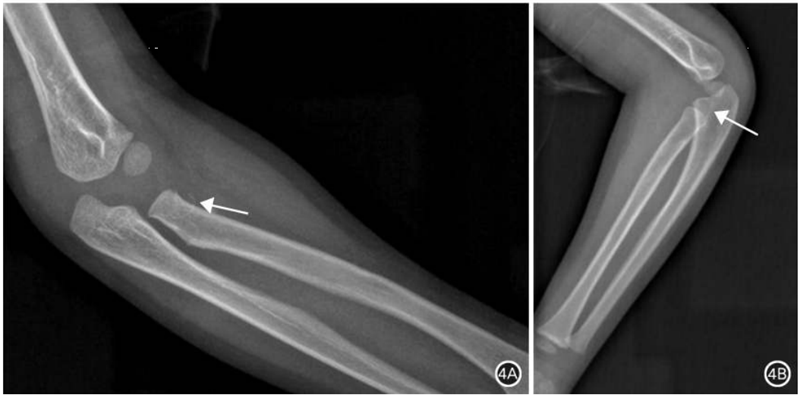

图4 桡骨颈骨骺分离骨折。A.正位X线片隐约可见桡骨近端移位翻转撕脱骨折片(箭头所示),关节软骨不可见;B.侧位X线片示疑似重叠骨折影,尺骨近端遮挡明显(箭头所示)